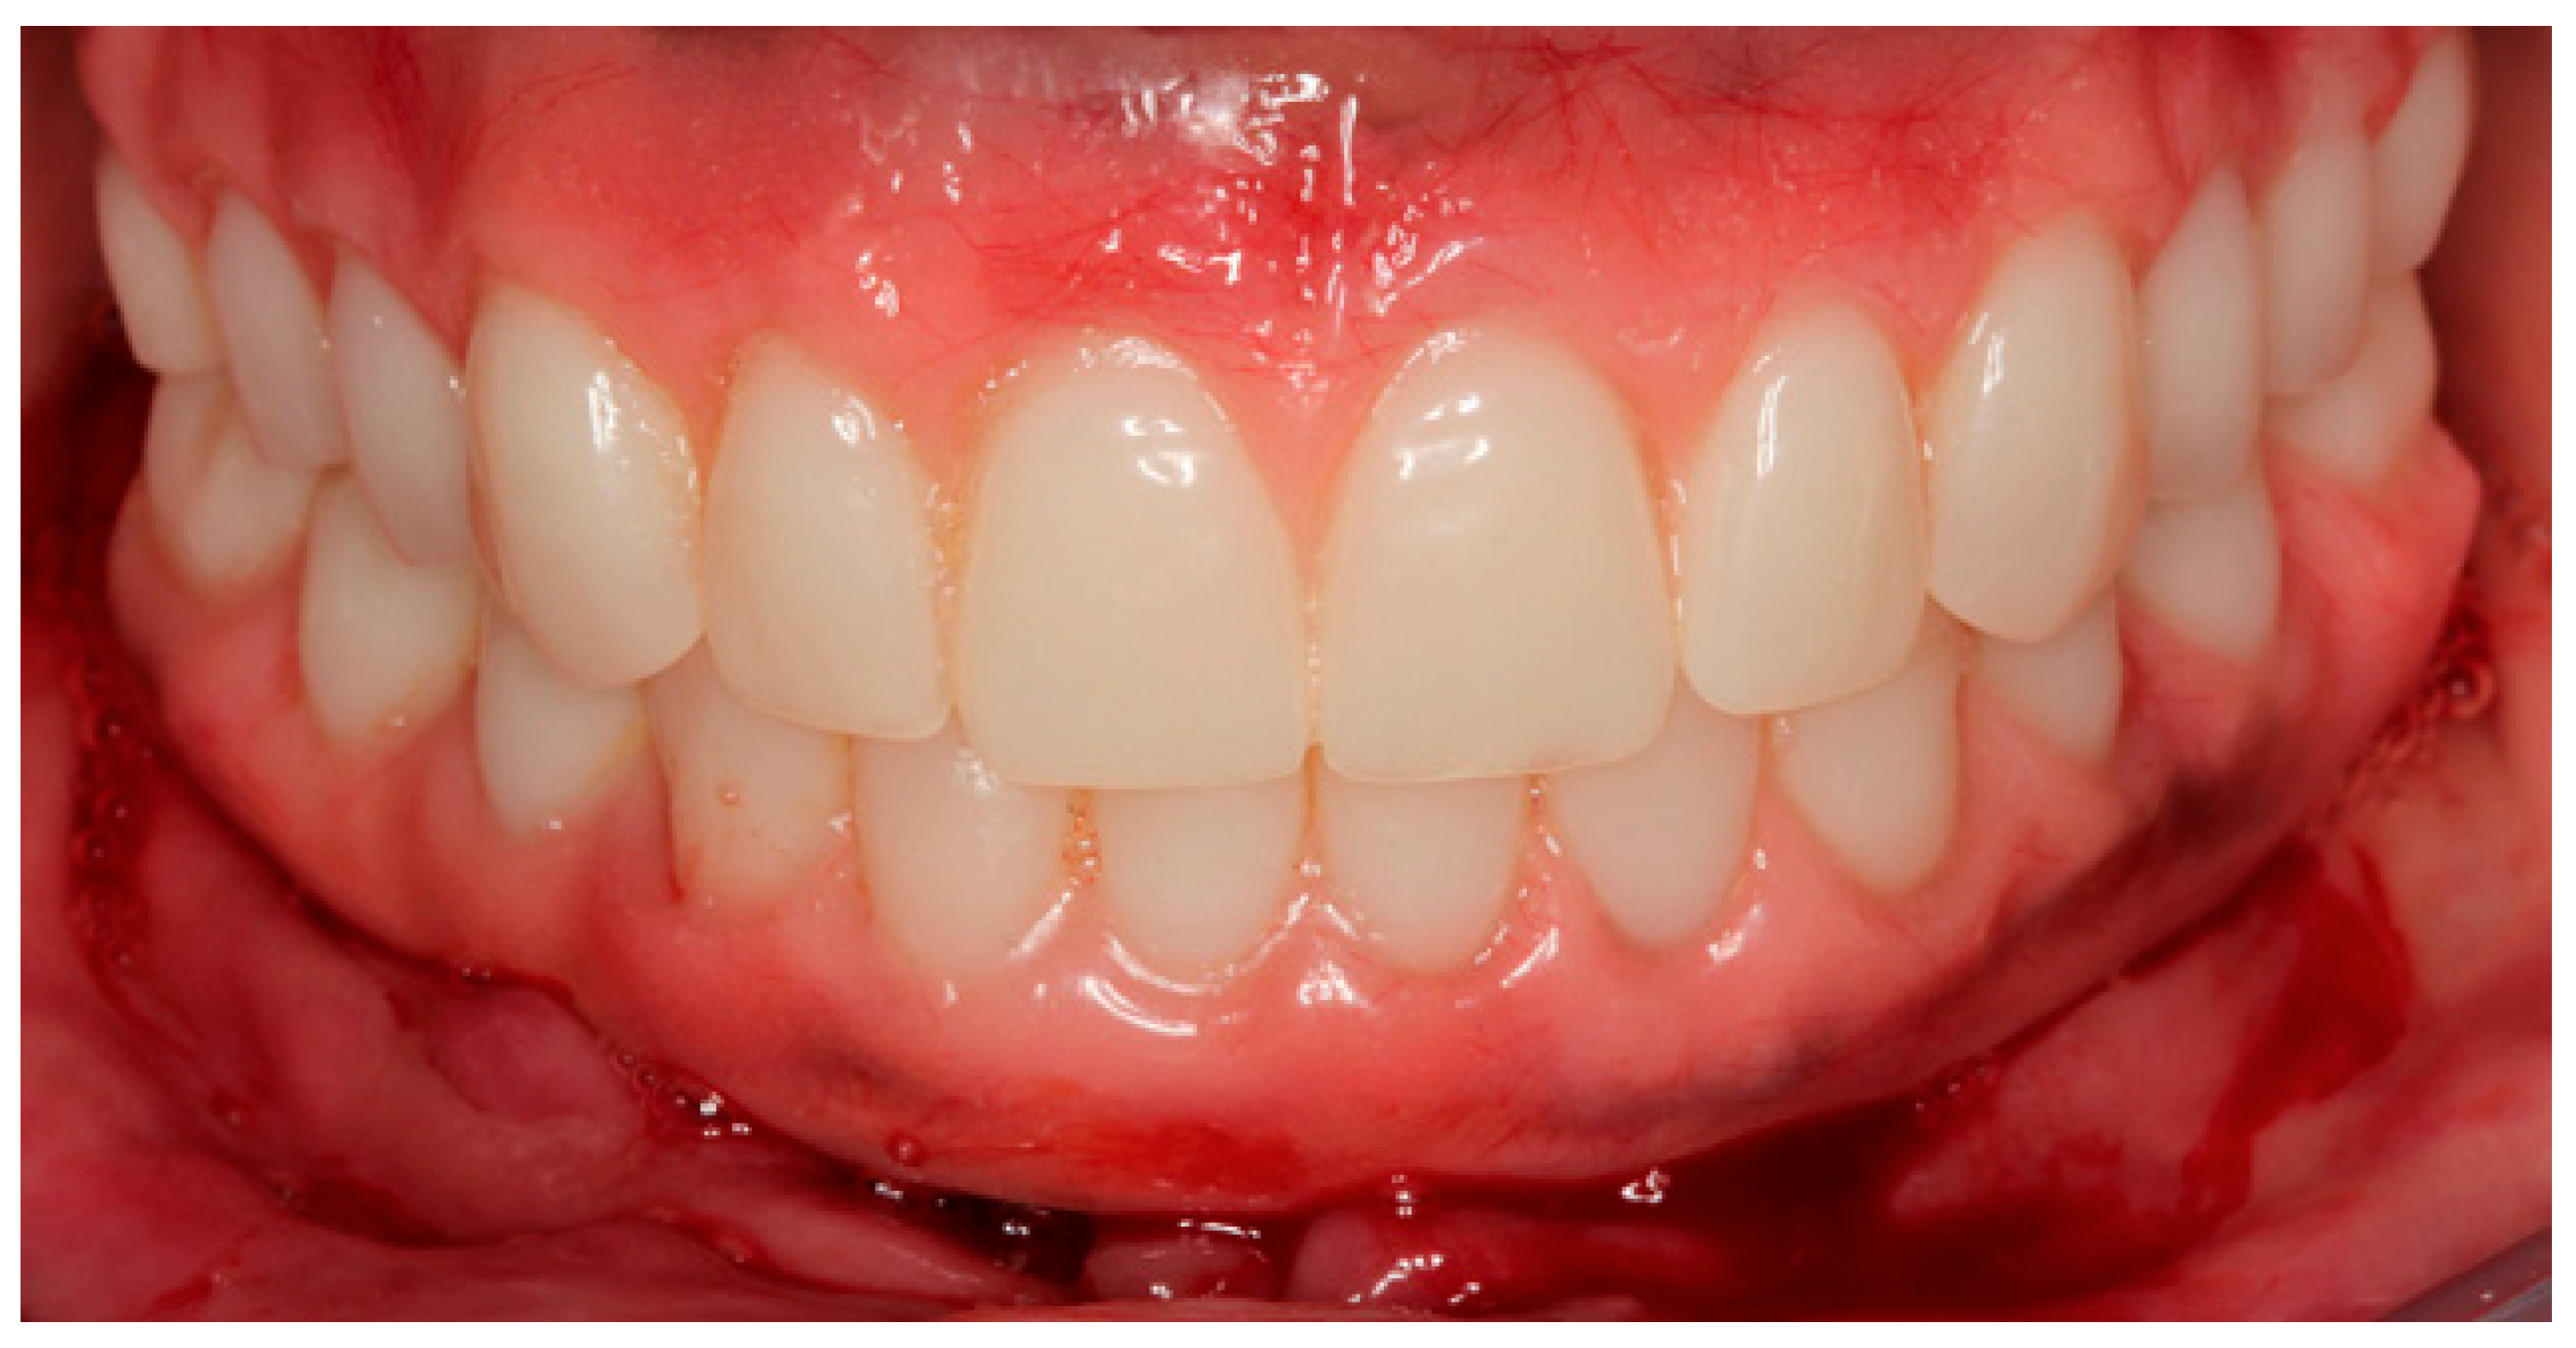

Figure 12.

Buccal view of rehabilitations of both arches according to the All-on-Four concept 48 h after surgery.